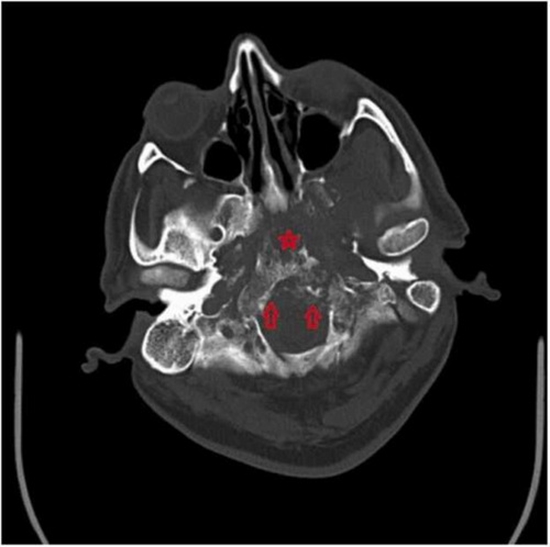

Skull base osteomyelitis: A case report of Garcin syndrome due to mucormycosis in COVID pandemic

Garcin syndrome is characterized by progressive unilateral multiple cranial nerve palsy without the presence of intracranial hypertension. In this case, we present a patient who experienced lower cranial nerve (CN 9–12) involvement attributed to post-mucormycosis osteomyelitis of the skull base. The osteomyelitis resulting from mucormycosis led to the development of Garcin syndrome, which manifested as progressive paralysis of the cranial nerves. It is important to recognize this rare complication and consider it in the differential diagnosis when evaluating patients with lower cranial nerve palsy following mucormycosis-related skull base osteomyelitis.